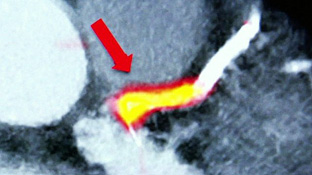

Có thể phát hiện nguy cơ đau tim bằng kỹ thuật chụp cắt lớp mới